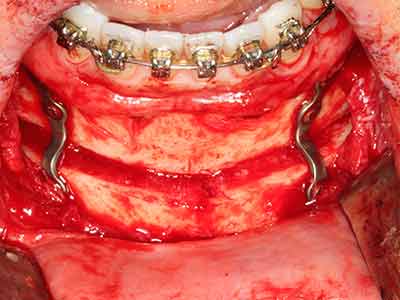

Fig. 16: The intraoral conditions are also stable with embedding of the implants in keratinized gingiva.

Indication: Bone splitting

Bone tissue is not simply a mineral structure but also contains a substantial proportion of collagen fibres. This means it not only has good compressive strength but also a degree of flexibility, which can be taken advantage of when performing bone augmentations. In the classical expansion procedure using bone splitting, the atrophied alveolar ridge is split longitudinally and carefully expanded after reaching an adequate osteotomy depth (Fig. 13-16), ideally without substantial removal of the periosteum (Brugnami, Caiazzo et al. 2014, Stricker, Fleiner et al. 2014). Screw and plate systems with increasing expansion distance have proven effective in separating the two bone lamellae while remaining below the fracture threshold. In general, residual bone widths of at least 3–4 mm are required (Chiapasco, Zaniboni et al. 2006) to guarantee adequate flexibility and sufficient bone coverage of the future implants. If necessary, a vertical relief osteotomy on one or both sides can improve flexibility. A combination with additional augmentation techniques, particularly on the buccal side, has been described as an alternative to the classical technique.

The splitting procedure is particularly atraumatic and there is no significant loss of dimension when using piezosaws, and there are no significant differences between implants in split jaws and implants in an alveolar ridge without a bone deficit (Chiapasco, Zaniboni et al. 2006, Danza, Guidi et al. 2009). However, sufficient continuous irrigation is essential, particularly with locally restricted and deep splitting to prevent thermal stress in the apical osteotomy regions.